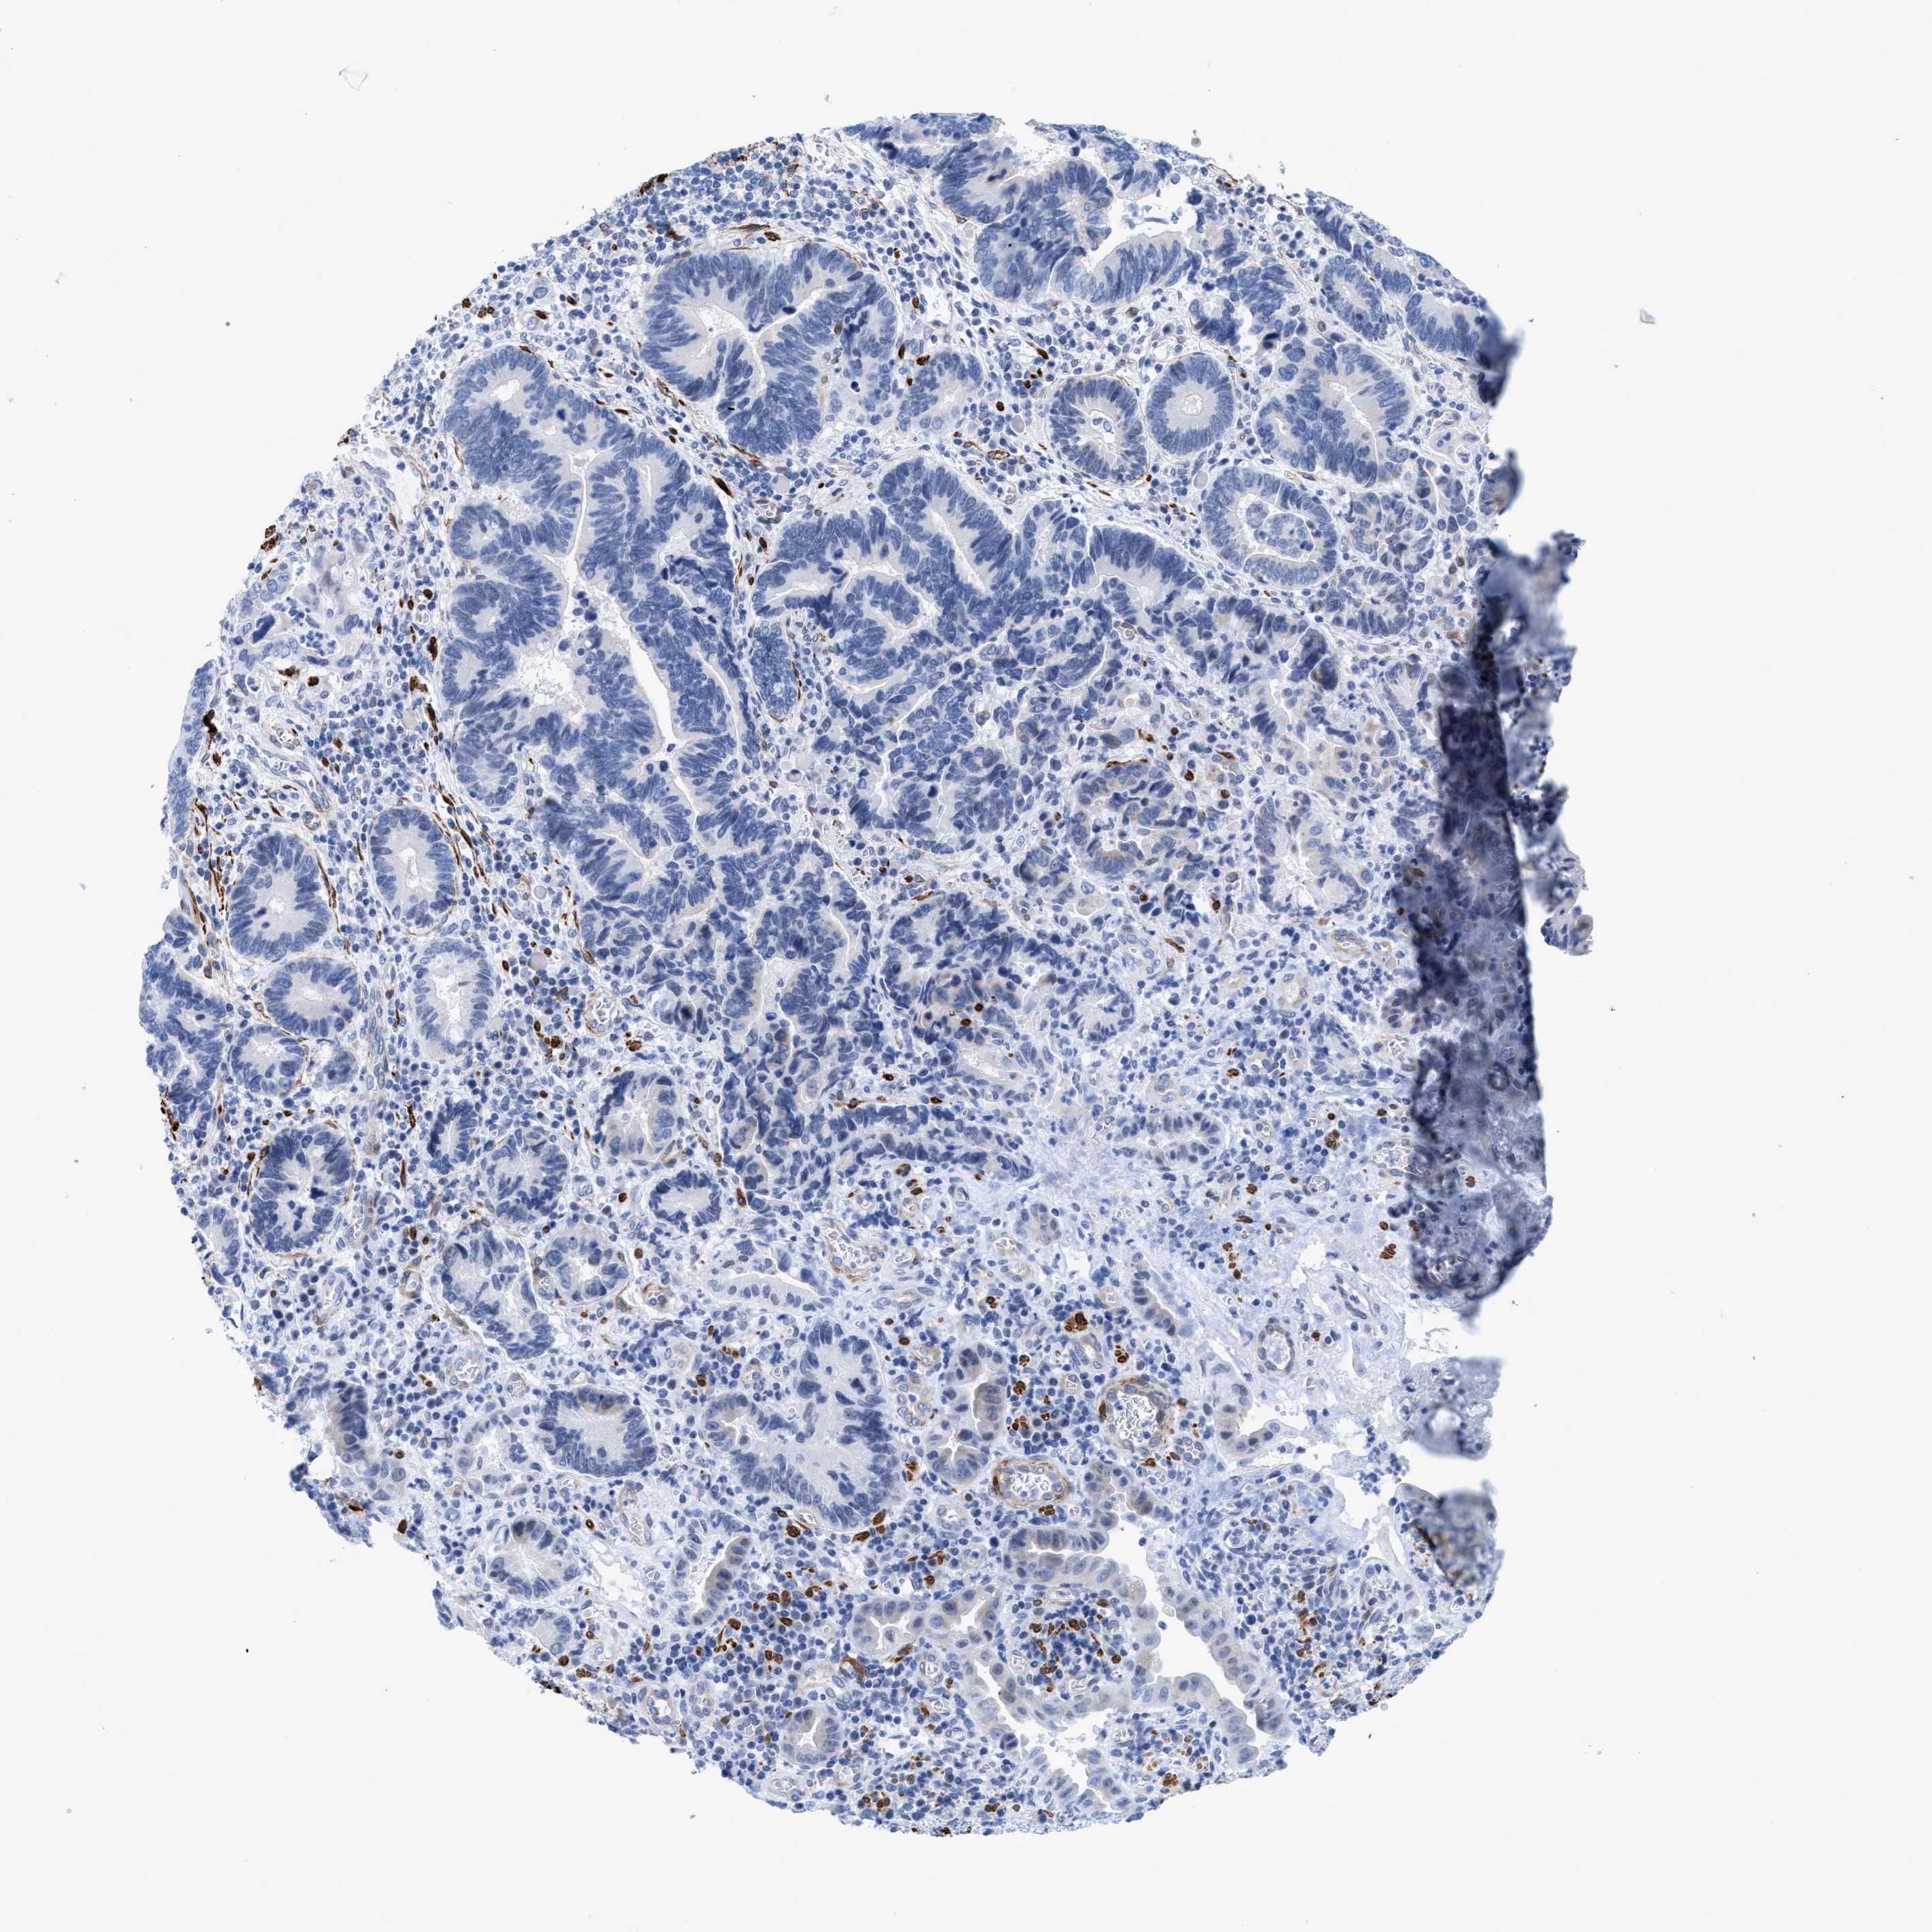

PANCREATIC CANCER - Protein expressioni

A mouse-over function shows sample information and annotation data. Click on an image to view it in a full screen mode. Samples can be filtered based on level of antibody staining by selecting one or several of the following categories: high, medium, low and not detected. The assay and annotation is described here.

Note that samples used for immunohistochemistry by the Human Protein Atlas do not correspond to samples in the TCGA dataset.

Antibody stainingi

Antibody staining in the annotated cell types in the current human tissue is reported as not detected, low, medium, or high, based on conventional immunohistochemistry profiling in selected tissues. This score is based on the combination of the staining intensity and fraction of stained cells.

Each image is clickable and will lead to virtual microscopy that enables deeper exploration of all samples and also displays staining intensity scores, fraction scores and subcellular localization as well as patient and tissue information for each sample.

Antibody HPA019467

Antibody HPA061657

Antibody CAB001447

Staining

High

Medium

Low

Not detected

Intensity

Strong

Moderate

Weak

Negative

Quantity

>75%

75%-25%

<25%

None

Location

Nuclear

Cytoplasmic/membranous

Cytoplasmic/membranous,nuclear

Adenocarcinoma, NOS